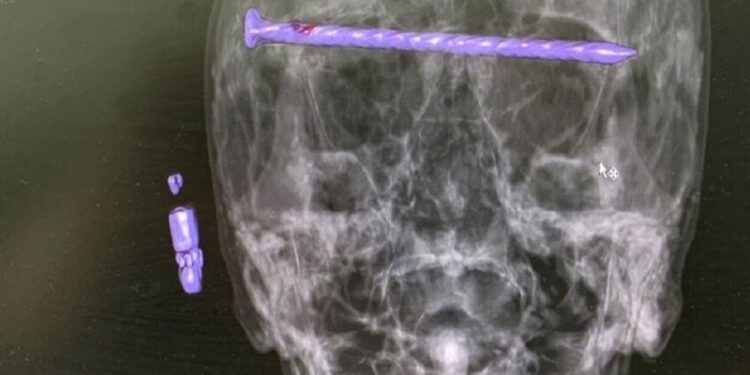

أخرج جراحون روس مسمار طوله 15 سم من رأس رجل في مدينة نيجني تاجيل، بمنطقة الأورال الروسية، وذلك وفقا لإدارة السياسة الإعلامية في محافظة سفيردلوفسك الروسية.

وتم نقل المريض إلى المستشفى مصابا بجروح خطيرة في الرأس بعد أن تعرض لحادثة سقوط على الأرض. وكشف التصوير المقطعي عن مسمار طوله 15 سم يمر بالصدغ الأيمن عبر محجر العين إلى الصدغ الأيسر. وأوضح الأطباء أن الوضع تفاقم بسبب تلف الجافية في الدماغ وضغط مقلة العين.